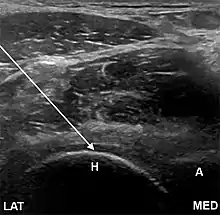

- The anterior longitudinal approach: the probe is aligned along the long axis of the femoral neck. The needle is introduced from an anteroinferior approach and is passed into the anterior joint recess at the femoral head-neck junction.

- The anterolateral approach, with the ultrasound probe oriented axially and the femoral head and acetabular rim in view. This often shortens the distance from needle skin entry to joint compared to the longitudinal approach making it a useful approach in larger patients. The introduced needle remains lateral to the femoral neurovascular bundle, and the needle is advanced until its tip rests on the femoral head.